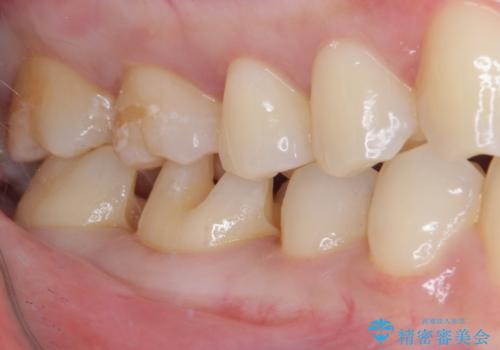

そして次の来院時、セラミックインレーを装着し、噛み合わせなどの調整を行います。

自然な色調で大変満足されました。